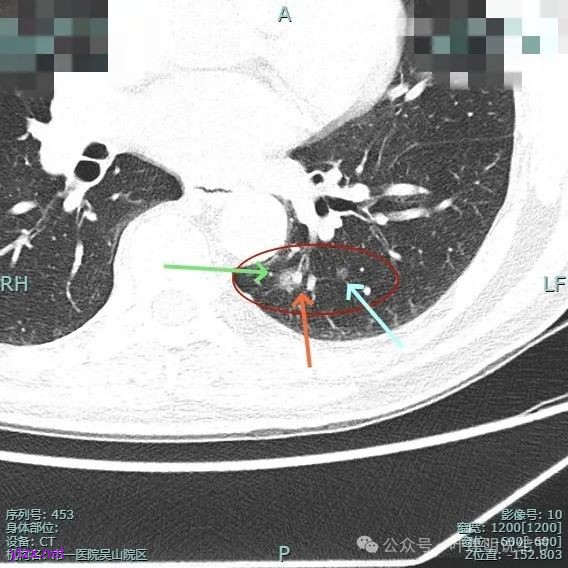

主病灶混合密度,血管进入;次病灶小且淡,但轮廓清。

手术组再三考虑,由于即使主病灶仍磨玻璃成分为主,是符合指南亚肺叶切除的指征的,如果能想办法定位后楔形切除,不按肺段解剖切,不单手术方便,而且也容易保留更多肺组织。所以与患方商量并沟通后,我们仍选择定位后的楔形切除,术前请影像科沈起钧主任定位,用医用胶定:

上图蓝色箭头所指的是医用定位胶,天蓝色箭头是次病灶,红色箭头是主病灶,设计的切除线如虚线所示。我们打算进胸后确定定位胶所在平面,因为包括两处病灶均在同一平面上,然后我们游离下肺韧带,将后基底段此部分肺组织向下解剖游离开,直到下肺静脉下缘,并贴着下叶静脉边缘往肺实质深面用切割缝合器切开并闭合肺切缘,按CT上大概距离推算,到越过次病灶深度后转向胸肋面,切除该范围内的肺组织。